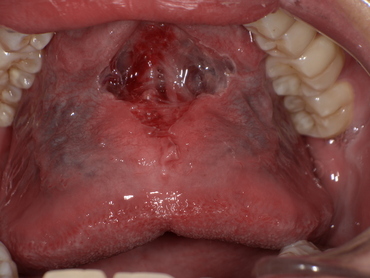

6. 症例紹介:滑舌が改善した20代男性のケース

● ご相談内容

ラ行・サ行の発音が不明瞭で、職場での会話にも影響していた20代男性。

診察の結果、舌小帯が短く、舌先が上あごに届かない状態でした。

● 治療内容

Before

舌小帯が短く、舌先を上あごまで十分に持ち上げることができません。